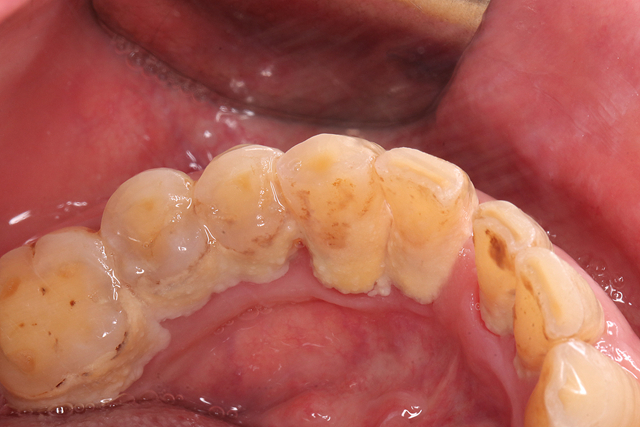

什么是牙结石长什么样子?

牙结石又称牙石,是长期附着在牙齿表面经过沉积和钙化形成的菌斑和软垢。它们通常呈黄色、褐色甚至黑色,主要在牙龈边缘,两颗牙齿之间或龋齿沟,呈现出大小各异的不同形状,甚至有的可以通过拉舌头而感知。